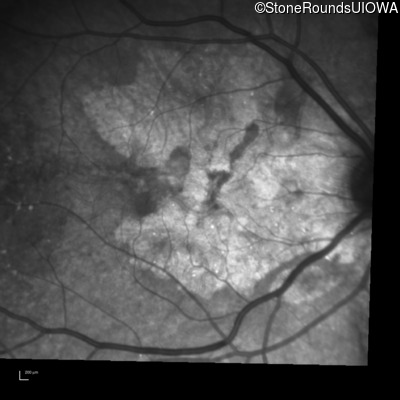

Infrared Fundus Photograph - Right - 20/20 -1

Exemplar

Infrared Fundus Photograph - Left - 20/20 -2